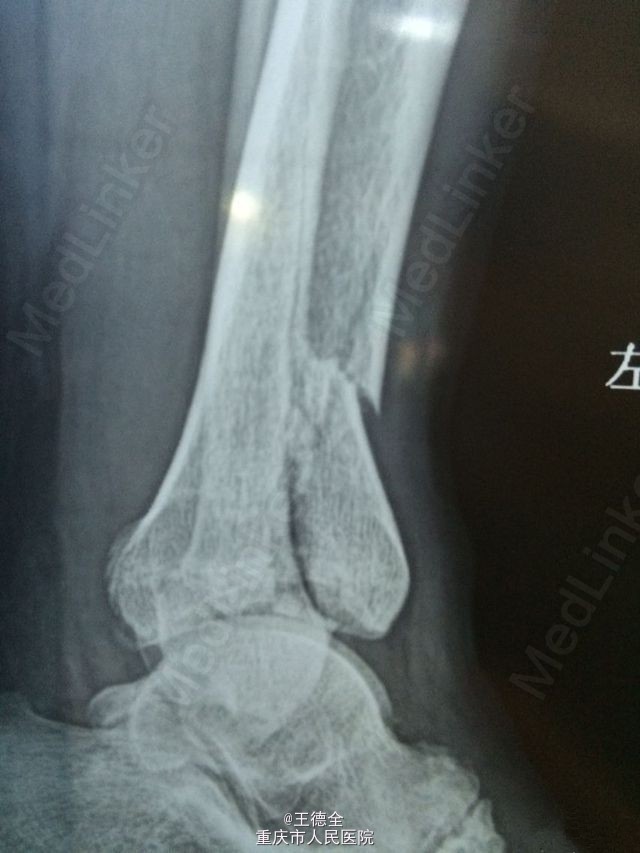

左脚pilon骨折一例

患者老年男性,高出摔落伤,查体:左踝部中度肿胀,畸形,压痛,活动受限,足背动脉波动好,足趾运动及末梢血运、感觉正常。